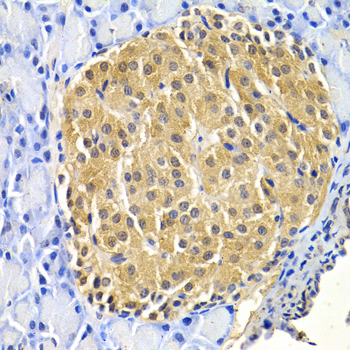

• A5762: image 2

Immunohistochemistry of paraffin-embedded rat pancreas using HTRA2 antibody at dilution of 1:200 (400x lens).